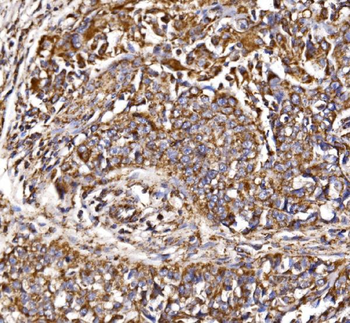

100 μl, 50 μl, 200 μl - ATF4 Recombinant Rabbit Monoclonal Antibody [orb704304]Featured

FC, ICC, IF, IHC-Fr, IHC-P, WB

Human

Rabbit

Recombinant

Unconjugated

50 μl, 100 μl - MARK3 Recombinant Rabbit Monoclonal Antibody [orb704310]Featured